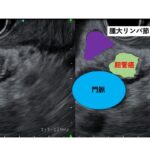

背部痛を主訴にエコーで発見した膵臓癌の一例